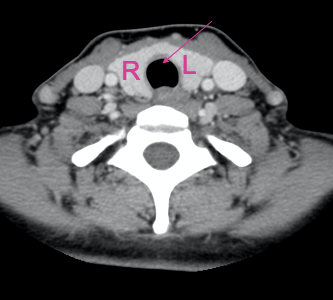

What is indicated by the arrow?

Oesophagus

Trachea